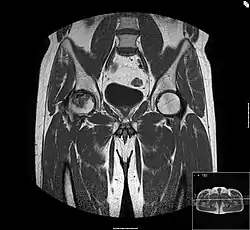

Bei dem Bild handelt es sich um eine MRT-Darstellung einer rechtsseitigen Femurkopfnekrose (links vom Betrachter). Ein scharf abgegrenzter Bezirk des Knochens ist ödematös verquollen, die Grenzschicht ist besonders auffällig, hier setzt sich der Körper mit dem Krankheitsprozess auseinander. Das linke Hüftgelenk ist normal, das erkennt man durch einfaches Vergleichen.